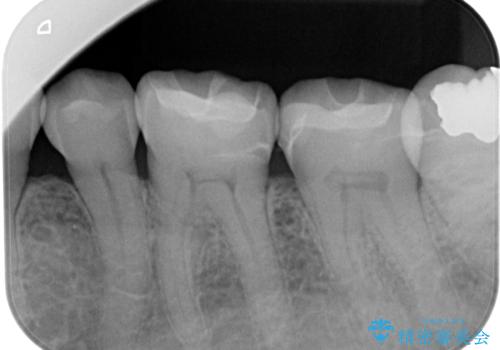

左下7番目の歯の詰め物が外れ、セラミックインレーでのやり替えとなりました。

隣在歯にも保険適用もメタルインレーが入っており、咬合面のインレーと歯質の境目が虫歯になっていたこともあり、合わせてのやり替えとなりました。

左下7番めの歯、フロスを通したらインレーが外れてしまったとのことで、適合具合の精密さや、これを機に白い詰め物にしたいとのことからセラミックインレーでのやり替えとなりました。

また、6番目の歯にも保険適用のメタルインレーが入っており、咬合面インレーと歯質境目にう蝕を認め合わせてのやり替えとなりました。